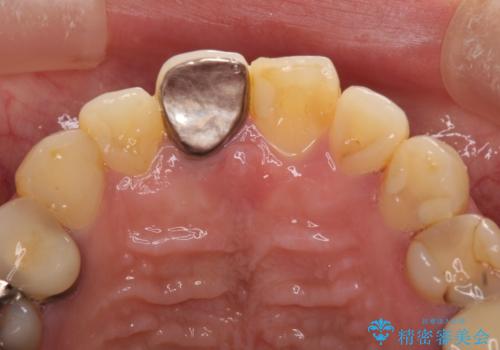

部分矯正を行った後にインプラント埋入と手前の歯の根管治療を行い、その後補綴治療を行うこととしました。

治療途中より、上の歯や反対側の銀歯、上顎前歯の色合いや下顎前歯のデコボコが気になってきたため、全てを治療することとしました。